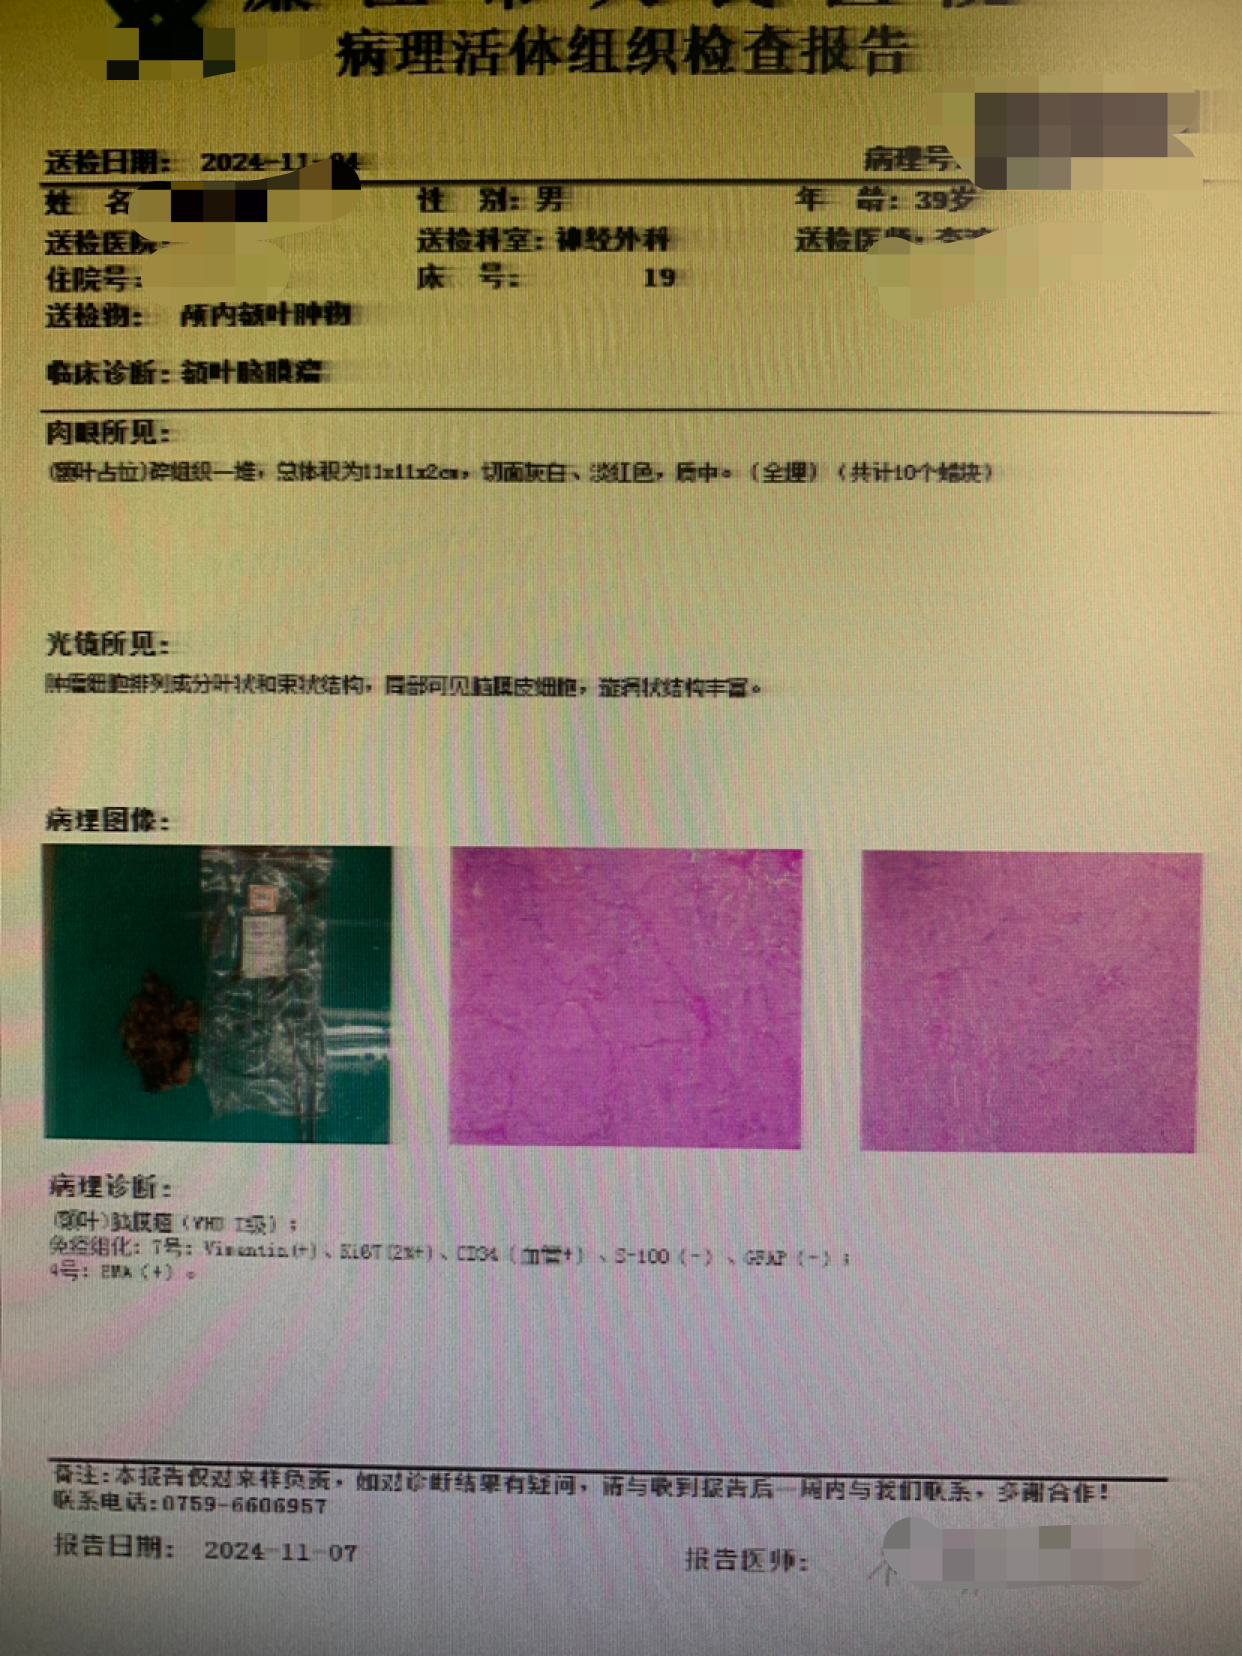

病例一:青年男性,突发昏迷2小时来诊。肢体抖动不适约2年,肢体乏力一个月,双膝疼痛4天。

术前CT

神志昏迷双瞳散大对光反射迟钝入院,入院后甘露醇脱水加地米静滴后患者神经功能有改善,能摸索定位,瞳孔反射改善。考虑占位大直接切除可能出血多,拟术前栓塞处理,但造影发现栓塞不易风险高后放弃栓塞。